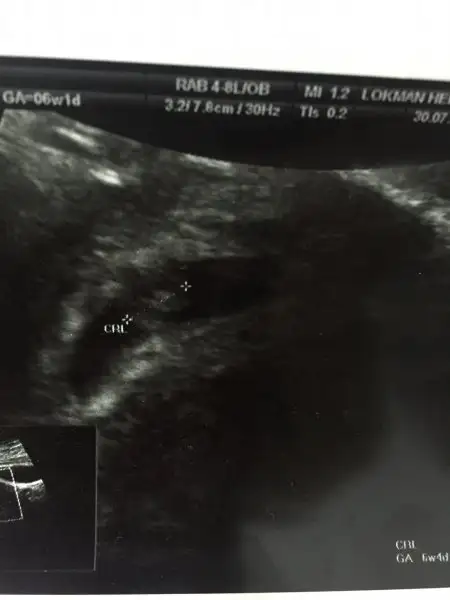

Canım o ölçümler net olmuyo genelde zaten birkaç hafta geri yada ileriKızlar benim usg de6+6 haftalık diyor ben 7+1 imi 2 gün artı eksisi var zaten.. tammyumırtşaöa dönemine denk gelmiş demek ki.. crl 8.9 mm diyor merak eden arkadaşlara bebekte iki art arasındakiymiş

İnternetten araştırdım hamilelikte rahim düzeliyormuş bebek büyüdükçe, Doğumdan sonra geri eski haline geliyormuş tek eksisi görüntü netliği olmuyormus fena değil ama ultrason görüntüsü zaten çok net olmuyorlar ki ekledim ilk fotosunu miniğimin![]()

Canim hangi lokman hekime gidiyorsun hangi doktor memnunmusunEki Görüntüle 2175360